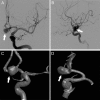

Figure 5. UIATS case recommendation resulting in the lowest agreement among the internal and external reviewer cohorts

Corresponding scores in accordance with unruptured intracranial aneurysm treatment score (UIATS) features are given in parentheses. A catheter angiogram of a 25-year-old woman (4 points favoring treatment for patient age younger than 40 years) who previously underwent MRI for persistent headaches, vertigo, and occasional bitemporal vision disturbances (due to a migraine aura) with (A) posterior-anterior and (B) lateral projection as well as (C) posterior-anterior and (D) lateral 3-dimensional reconstructions is shown. This left-sided wide-necked paraophthalmic internal carotid artery aneurysm had a maximum diameter of 3 mm with a neck diameter of 2.7 mm (3 points favoring conservative management for aneurysm complexity due to wide neck). The patient did not report any additional risk factors or comorbidities in her past medical history. The resulting scores based on the UIATS were 4 points in favor of aneurysm repair and 8 points (including 5 points favoring conservative management for the constant intervention-related risk) in favor of conservative management. The resulting UIATS recommendation was “conservative management.” Overall agreement with this UIATS recommendation was 3.7 (95% confidence interval 3.44–3.96) for both reviewer cohorts.